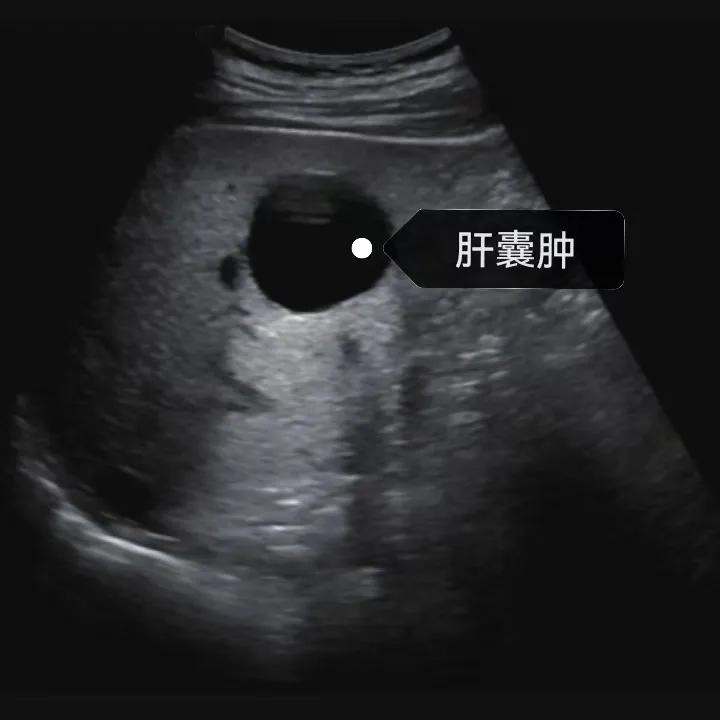

漯河市中醫(yī)院健康科普:認識肝囊腫

隨著人們健康意識的提升,越來越多的人每年會進行健康體檢,由于腹部(肝膽胰脾)超聲作為常規(guī)體檢項目之一, 肝囊腫的檢出率也愈發(fā)升高,大部分人對“腫”字都比較困惑,今天我們就來一起了解一下肝囊腫。

肝囊腫是一種常見的肝臟良性疾病,呈圓形或橢圓形,外由上皮細胞包裹形成包膜,內(nèi)由清亮、無色、無細胞成分的囊液填充,看上去就像是一顆注滿了水的氣球,因此通俗一點說就是肝臟中的“水泡”。

04、如何發(fā)現(xiàn)肝囊腫

超聲通常是診斷肝囊腫的首選方法,彩超對肝囊腫的檢出率可達98%,<1cm的囊腫也可檢出。肝囊腫常表現(xiàn)為圓形或橢圓形無回聲,包膜光滑完整,邊界清晰,可有側(cè)壁回聲失落征象,后方回聲增強。病程長、囊腫較大者或囊內(nèi)有過出血、感染者,無回聲腔內(nèi)可見少量絮狀回聲漂浮。超聲對肝囊腫的診斷準確而靈敏,且方法簡單、無創(chuàng)、費用低、可重復性高,因此常常被作為首選。